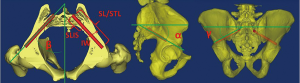

In order to illustrate the feasibility of the S2AI screw fixation and provide instructive data, several anatomic studies were conducted on computed tomography (CT) and cadaveric specimens (11,13-16). Parameters measured included (Figure 1): SL/STL: screw length or screw trajectory length; SLIS: screw length of the intrasacral part; IW: iliac width as defined by the narrowest iliac width measured between the inner cortices in the transverse plane; α: angle between screw trajectory and horizontal line in the sagittal plane; β: lateral trajectory angulation in the transverse plane; and γ: angle between screw trajectory and middle vertical line in the coronal plane. Typical S2AI screw trajectory parameters published previously (11-14,17) are summarized in Table 1. The angle between screw trajectory and horizontal line in the sagittal plane ranges from 27.5° to 48.8°, and averages 27.5° to 39.0°. The lateral trajectory angulation in the transverse plane ranges from 30.8° to 67.3°, and averages 32.4° to 52.2°. The angle between screw trajectory and middle vertical line in the coronal plane ranges from 19° to 49.2°, and averages 29.0° to 34.6°.